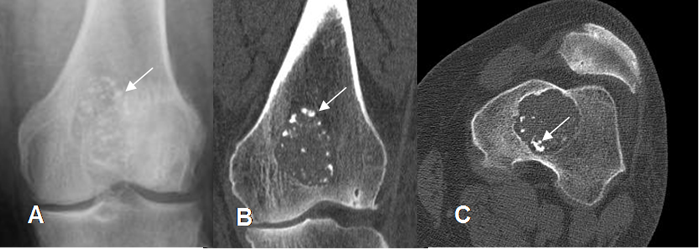

Fig 87. Encondroma.

A: Rx AP, B: TAC reconstrucción coronal y C: TAC axial. Lesión lítica central, de bordes definidos y calcificaciones condroides periféricas, por encondroma.